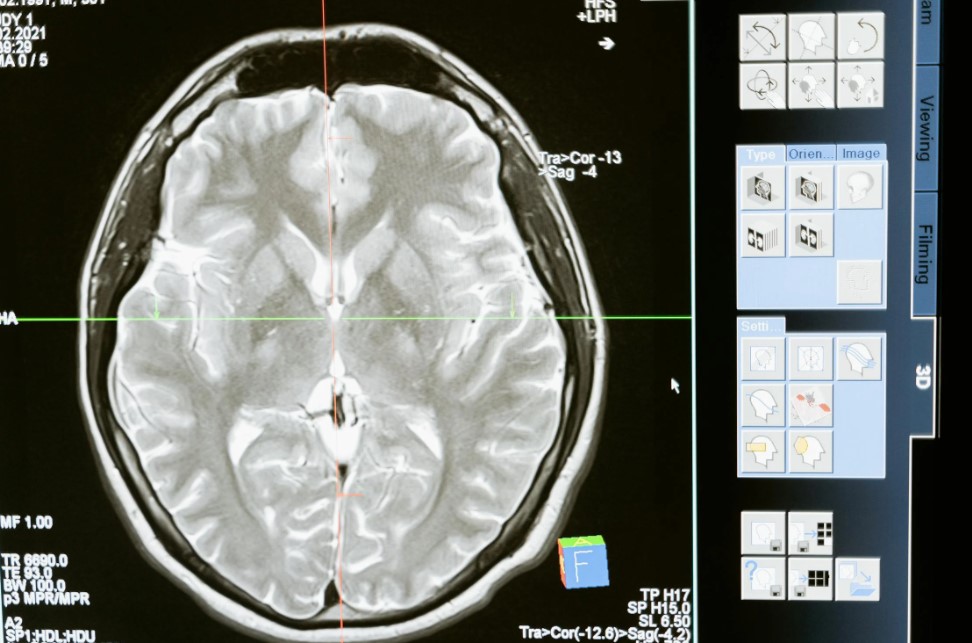

For example, after a serious accident, a patient with traumatic brain injury could be brought to hospital and undergo detailed brain imaging. Based on this scan, clinicians could inject magnetoelectric nanoparticles directly into the affected regions, in quantities tailored to the individual patient.